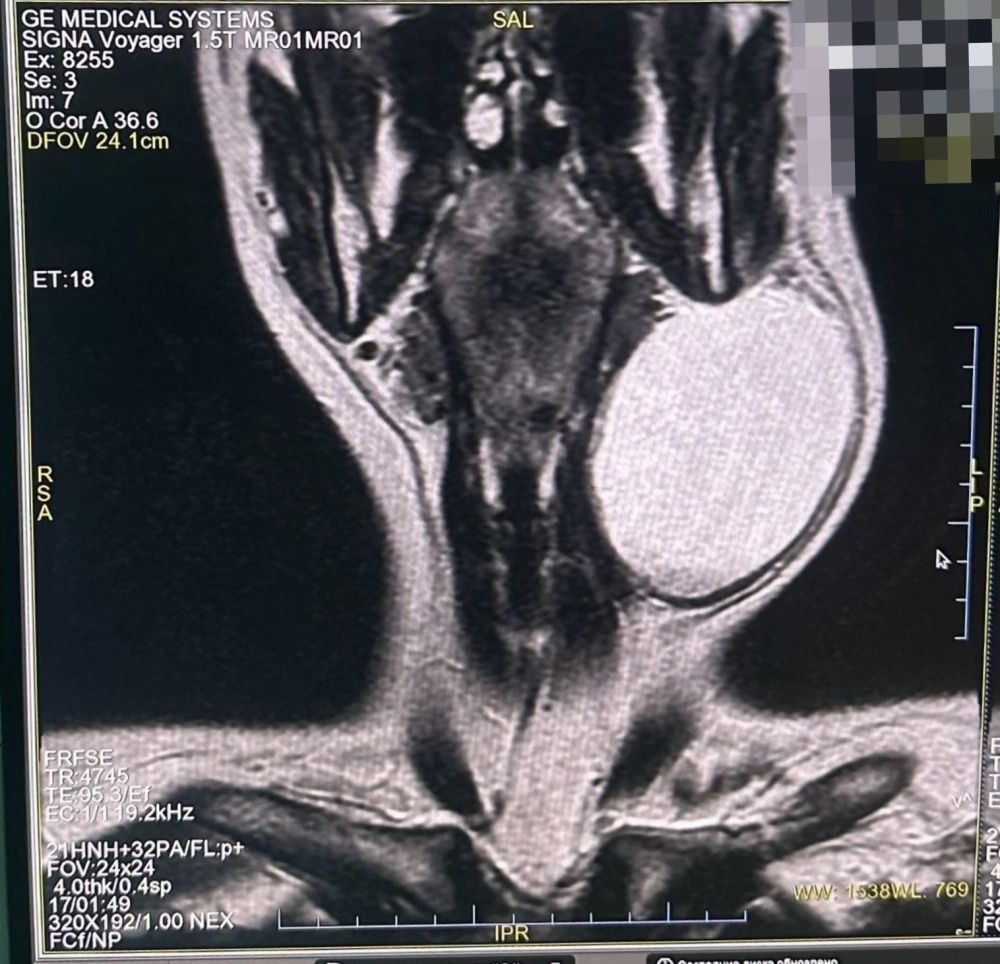

После проведения магнитно-резонансной томографии, было принято решение провести оперативное лечение - иссечение новообразования.

Его размеры составили 10,0 х 8,0 х 8,0 см, а объем извлеченной жидкости был равен 200 мл!